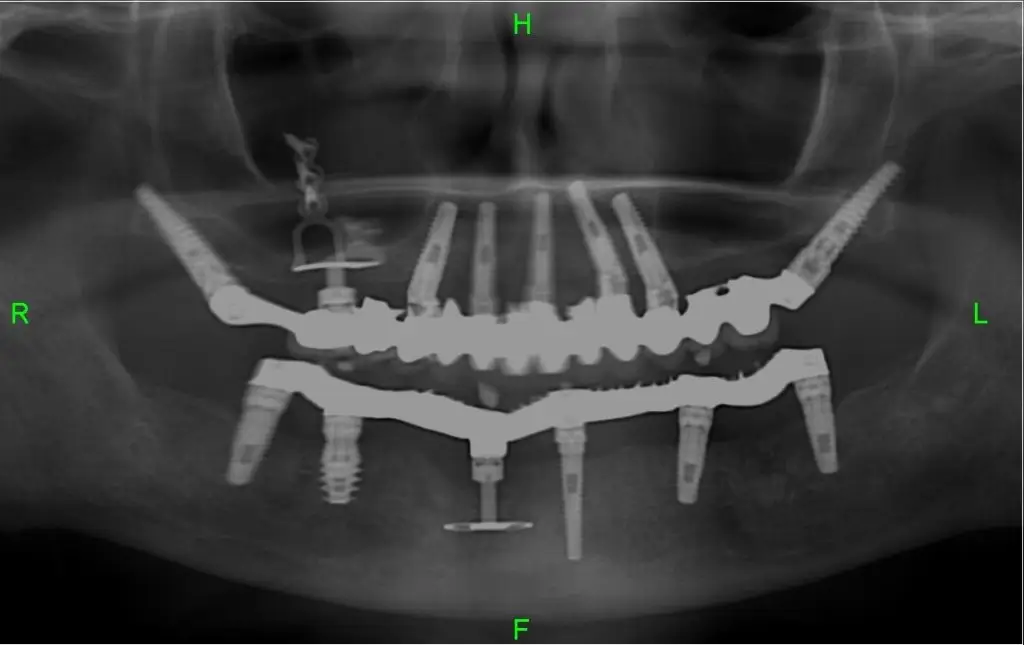

שתלי דיסק בשונה משתלים סטנדרטיים אינם בנויים בצורת בורג אלא יש להם בסיס שטוח בצורת דיסק ומכאן שמם. את שתלי הדיסק מחדירים מצידי הלסת ולא בהחדרה אנכית וכך מאפשרים להם להתקבע במקומות שבהם יש מחסור של עצם.

שתלים בזאליים או שתלי הדיסק אינם יכולים להחזיק לבד מערכת של שיניים ולכן השימוש בהם נעשה על ידי השתלת שיניים משולבת שבה נעזרים בשתלים דנטליים רגילים המעוגנים לאזורים בעצם הלסת שבהם יש מספיק עובי לעצם ואילו באזורים הדקים של העצם נעשה שימוש בשתלי דיסק.

שילוב שני סוגי השתלים מסייע להשיג יציבות גבוהה למערכת השיניים החדשה בלי ליצור דלקות או פגיעה מיותרת באזור החניכיים.